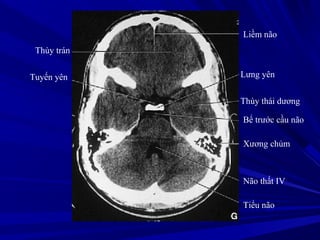

Liềm não

Lưng yên

Thùy thái dương

Bể trước cầu não

Xương chủm

Não thất IV

Tiểu não

Thùy trán

Tuyến yên